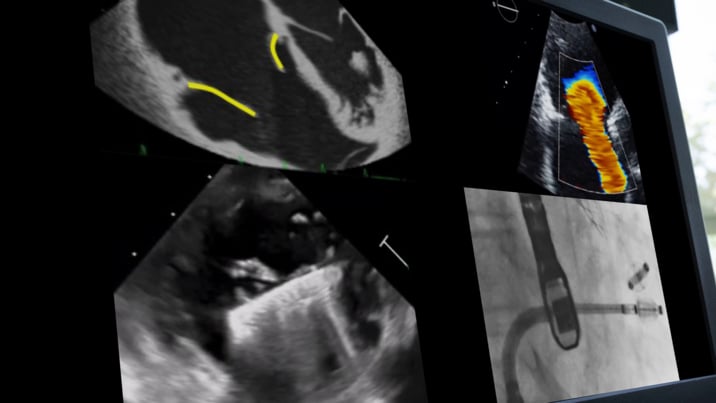

Delve into the forefront of tricuspid interventions as we present a compilation of enlightening webinars hosted in collaboration with the PCR Tricuspid Focus Group. Explore the latest advancements, gain valuable knowledge, and stay connected with the pulse of tricuspid interventions through these engaging webinars.